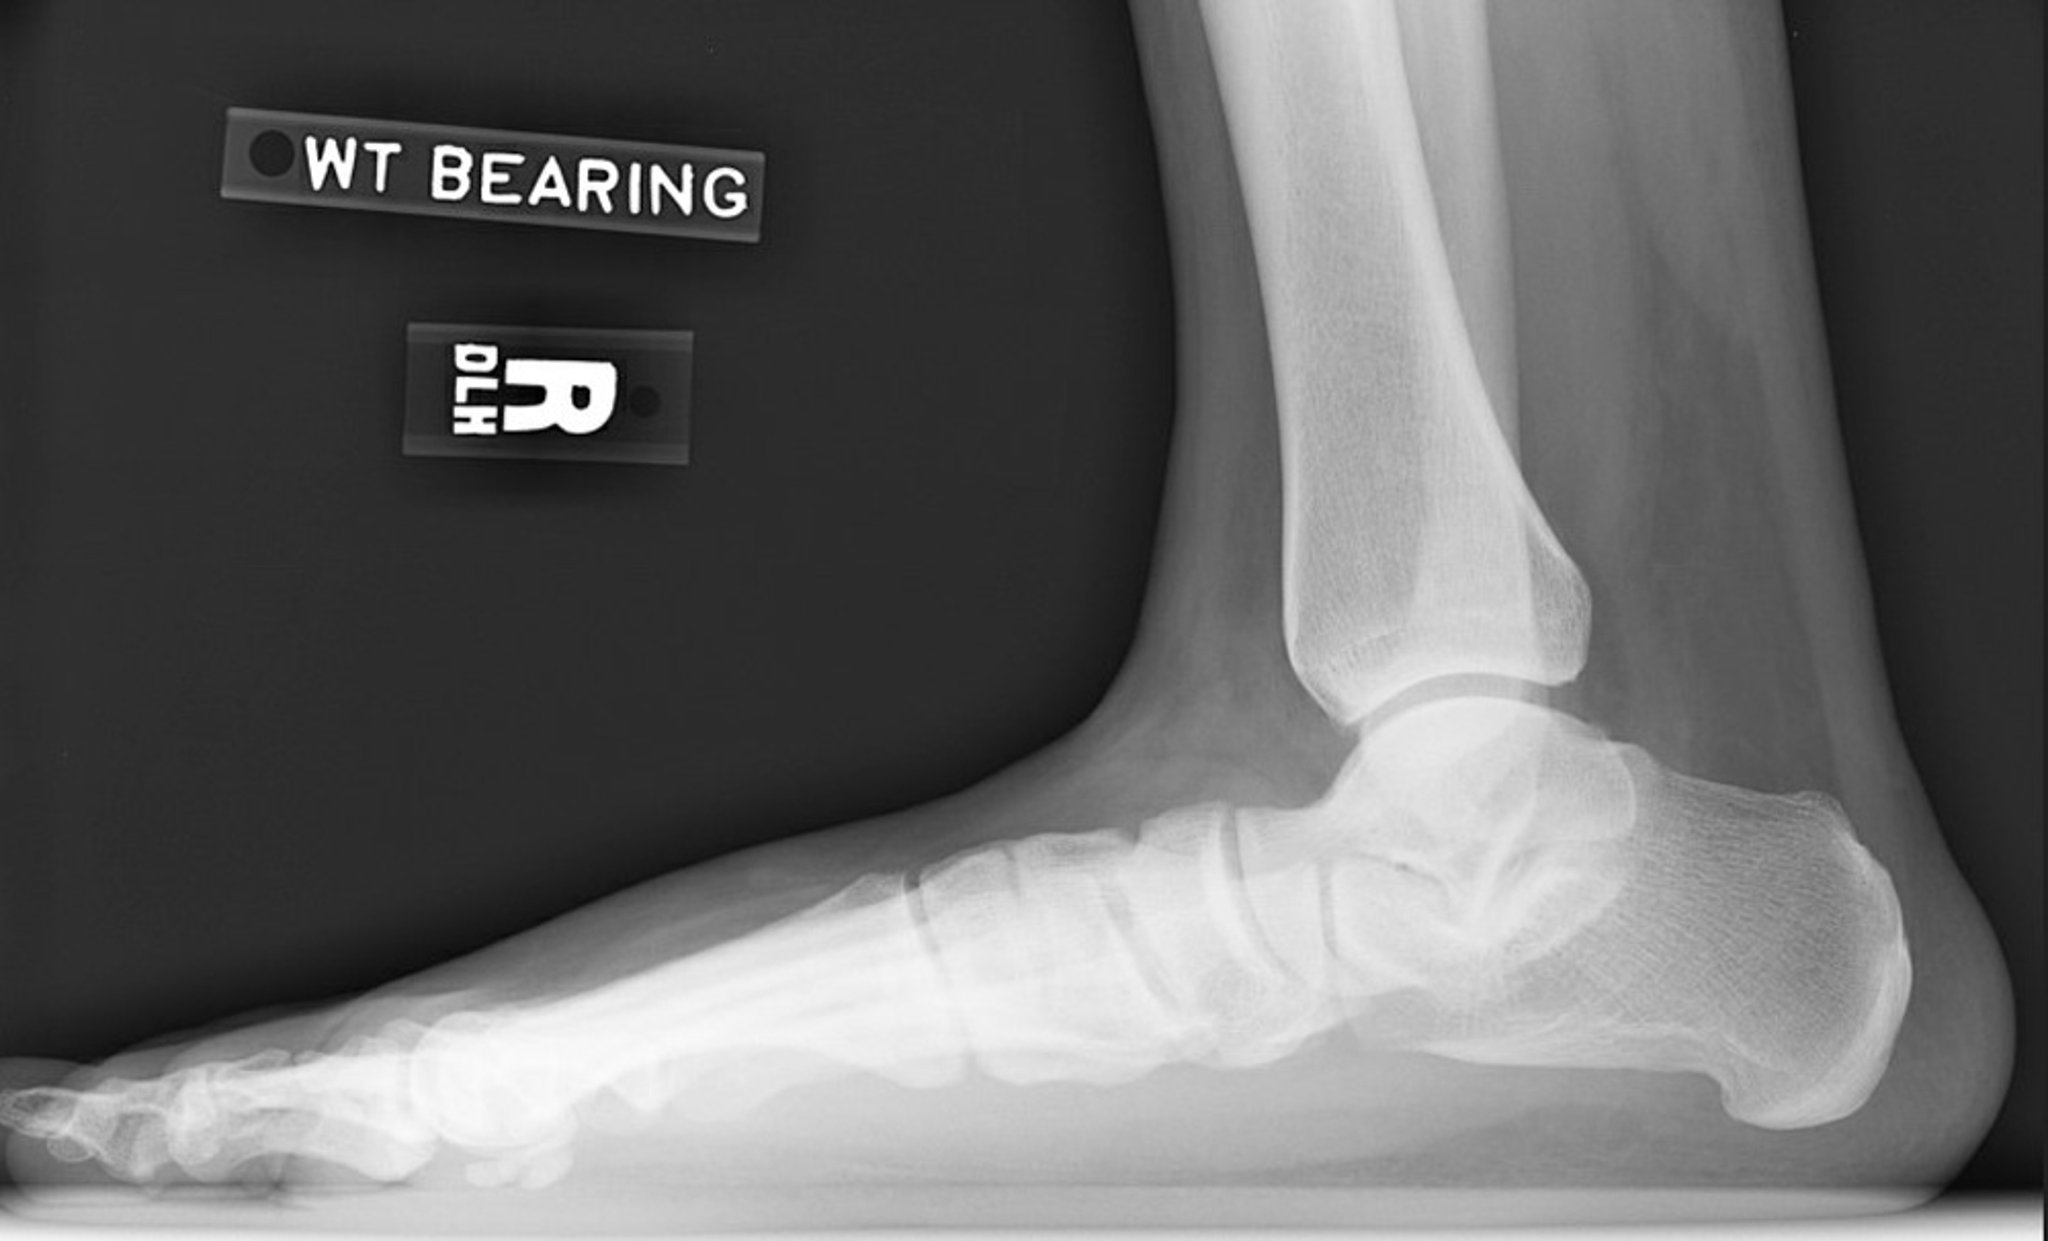

Radiografía de pie plano

Radiografía lateral del pie derecho que muestra pérdida de la altura del arco. Obsérvese la disminución del ángulo de inclinación del calcáneo y del ángulo de declinación astragalina. La articulación subtalar se estrecha, pero la articulación del tobillo está relativamente preservada.

Image courtesy of James C. Connors, DPM.